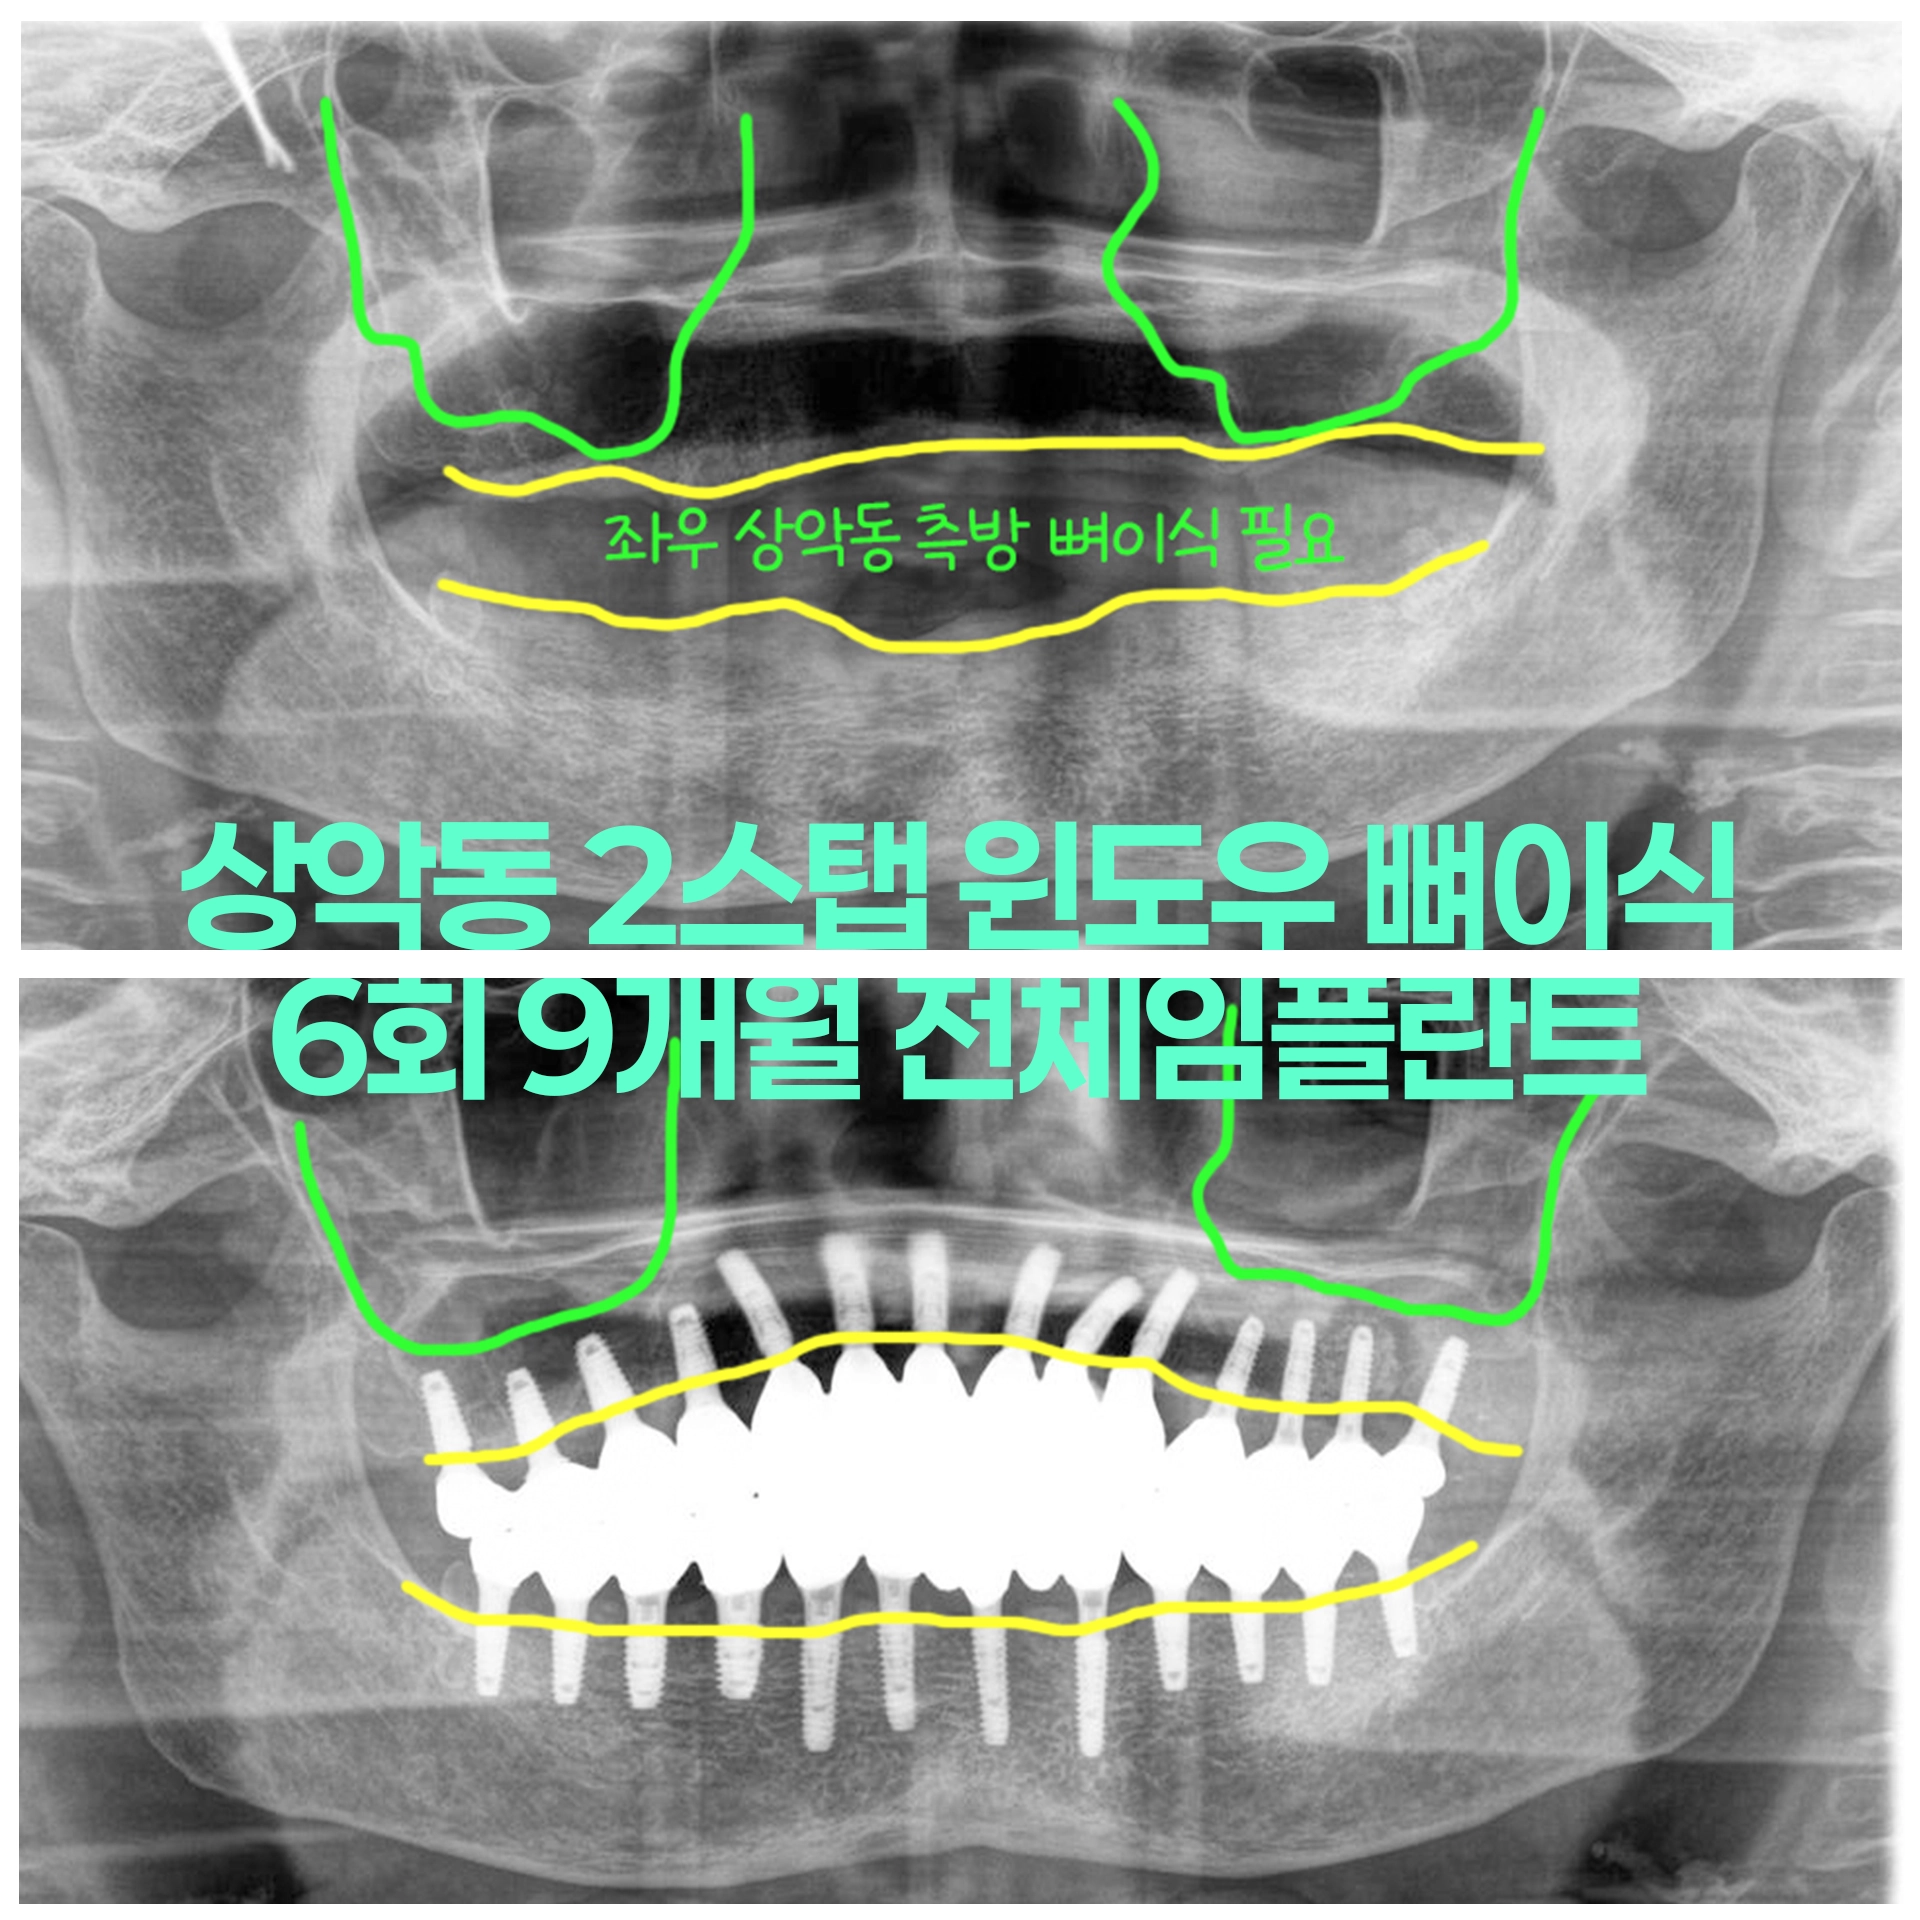

50대 여성 심한 치주염 치아 발치후 상악동 윈도우뼈이식 즉시하중 당일임시치아 전체임플란트